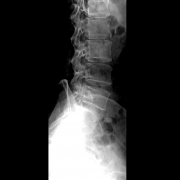

X线片有哪些伪影

X 线片伪影是指在 X 线影像中出现的与被检查物体真实形态和结构不相符的影像,主要包括以下几类: 设备相关伪影 运动伪影:X 线曝光过程中,患者自主或不自主的运动,如呼吸、心...更多 -

DR常见伪影及其形成原因

DR(Digital Radiography)即数字 X 线摄影,常见伪影及其形成原因如下: 运动伪影 原因 患者运动:患者在曝光过程中不能保持静止,如呼吸运动、心脏搏动、胃肠道蠕动以及不自主的肌肉...更多 -